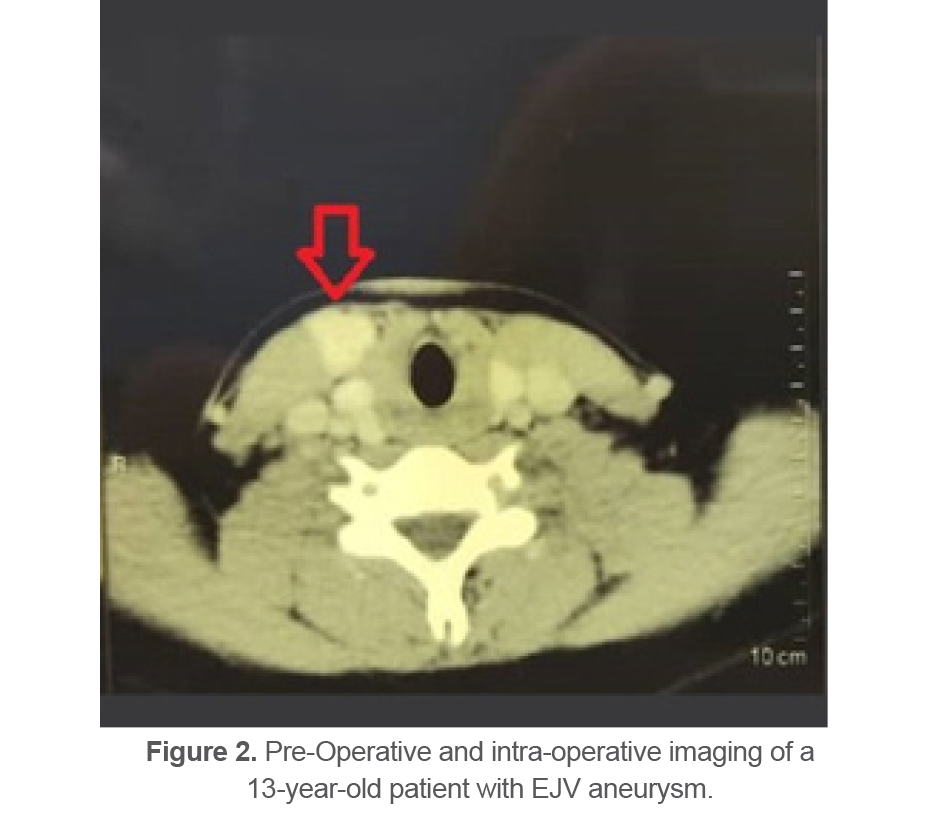

6 aneurysms were located in the External Jugular Vein (EJV) (Figures 2 and 3).

Figure 2. Pre-Operative and intra-operative imaging of a 13-year-old patient with EJV aneurysm.